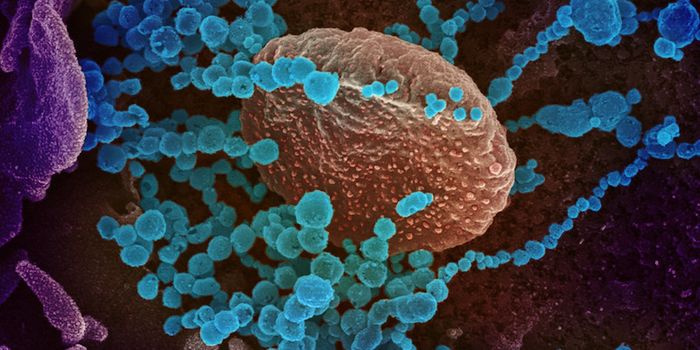

MAR 22, 2020MicrobiologyMore data is being gathered from an unfortunate and dramatic rise in the number of COVID-19 cases around the world.

APR 01, 2020MicrobiologyThere are a couple of different kinds of tests that researchers will be developing and clinicians will be using to disru ...

MAY 03, 2020Genetics & GenomicsThe origin of SARS-CoV-2, the pandemic virus that causes COVID-19, has become politicized as leaders seek to place blame ...

JUL 06, 2020MicrobiologyThe pandemic coronavirus has caused a wide range of different symptoms, and as time goes on, we may find that it can hav ...

JUL 05, 2020Cell & Molecular BiologyThe pandemic virus SARS-CoV-2 enters the body through the respiratory system to cause the illness COVID-19. But we know ...